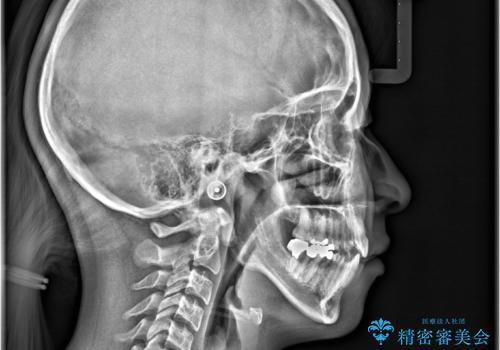

- 開咬と歯のデコボコ(叢生)、八重歯を主訴にご来院された患者様です。

矯正の精密検査の結果、上顎左右4番および下顎左右5番の計4本を抜歯し、ワイヤー矯正(クリア装置)にて治療を行いました。